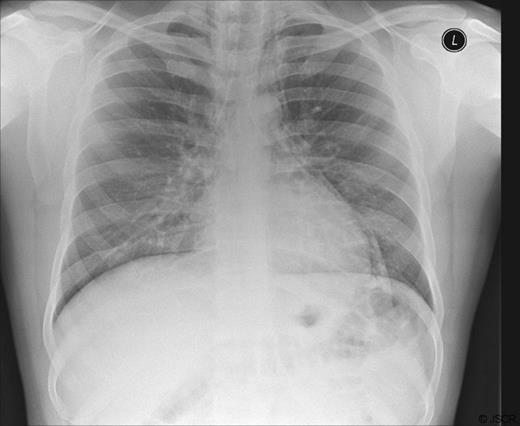

Two weeks after discharge from hospital he was readmitted with similar symptoms. Chest radiography did not reveal any pneumomediastinum. A gastrograffin contrast swallow showed no evidence of an esophageal leak. An upper GI endoscopy revealed oesophagitis for which he was commenced on a proton pump inhibitor. Therefore with the low probability of lung injury, a possible diagnosis of micro-perforation of the oesophagus was made. Once again, the patient was managed conservatively and was discharged a few days later symptom free.